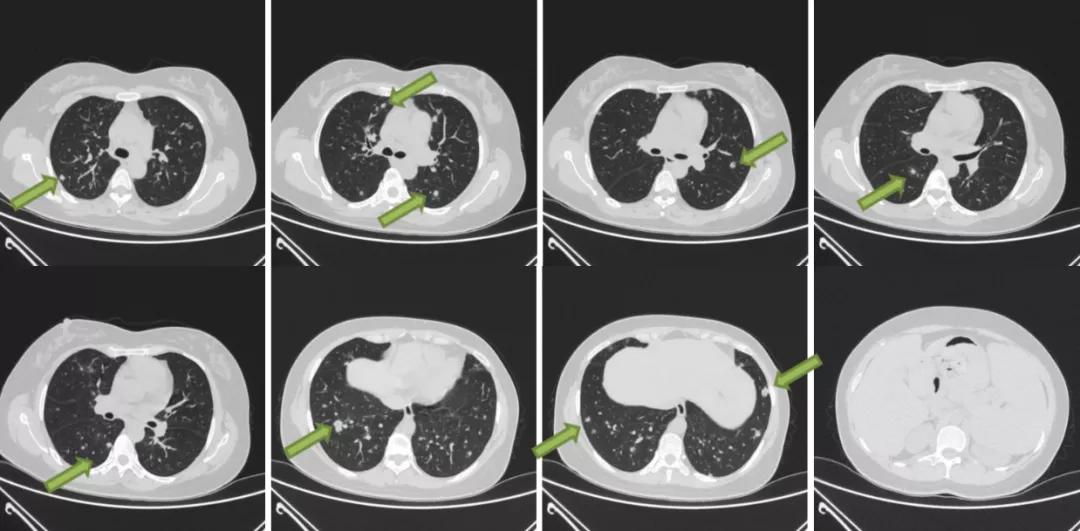

同日,行胸部CT显示:两肺多发结节、絮状影,性质待定,较8月27日(影像)片病灶增多、增大;纵隔、双侧腋窝小淋巴结;两肺局部少许炎症。

图6:胸部CT(2020.11.02)

胸部CT平扫+增强三维:1、双肺多发结节,突出病灶位于右肺下叶外基底段和左肺下叶前基底段。2、纵隔淋巴结肿大。3、肝脏钙化灶。4、右肾结石。5、脾大。双肺多发实性结节、玻璃结节,最大者位于右肺下叶外基底段(IM177),长径约1.7cm,边缘浅分叶,周围多发毛刺,内见含气支气管影。纵隔内可见数枚肿大的淋巴结。心脏大小未见明显异常,心包未见明显积液。双侧胸腔未见积液,胸膜未见增厚。肝内斑点状致密影,右肾结节状致密影,脾脏体积增大。

图7:胸部CT平扫+增强三维(2020/11/5)